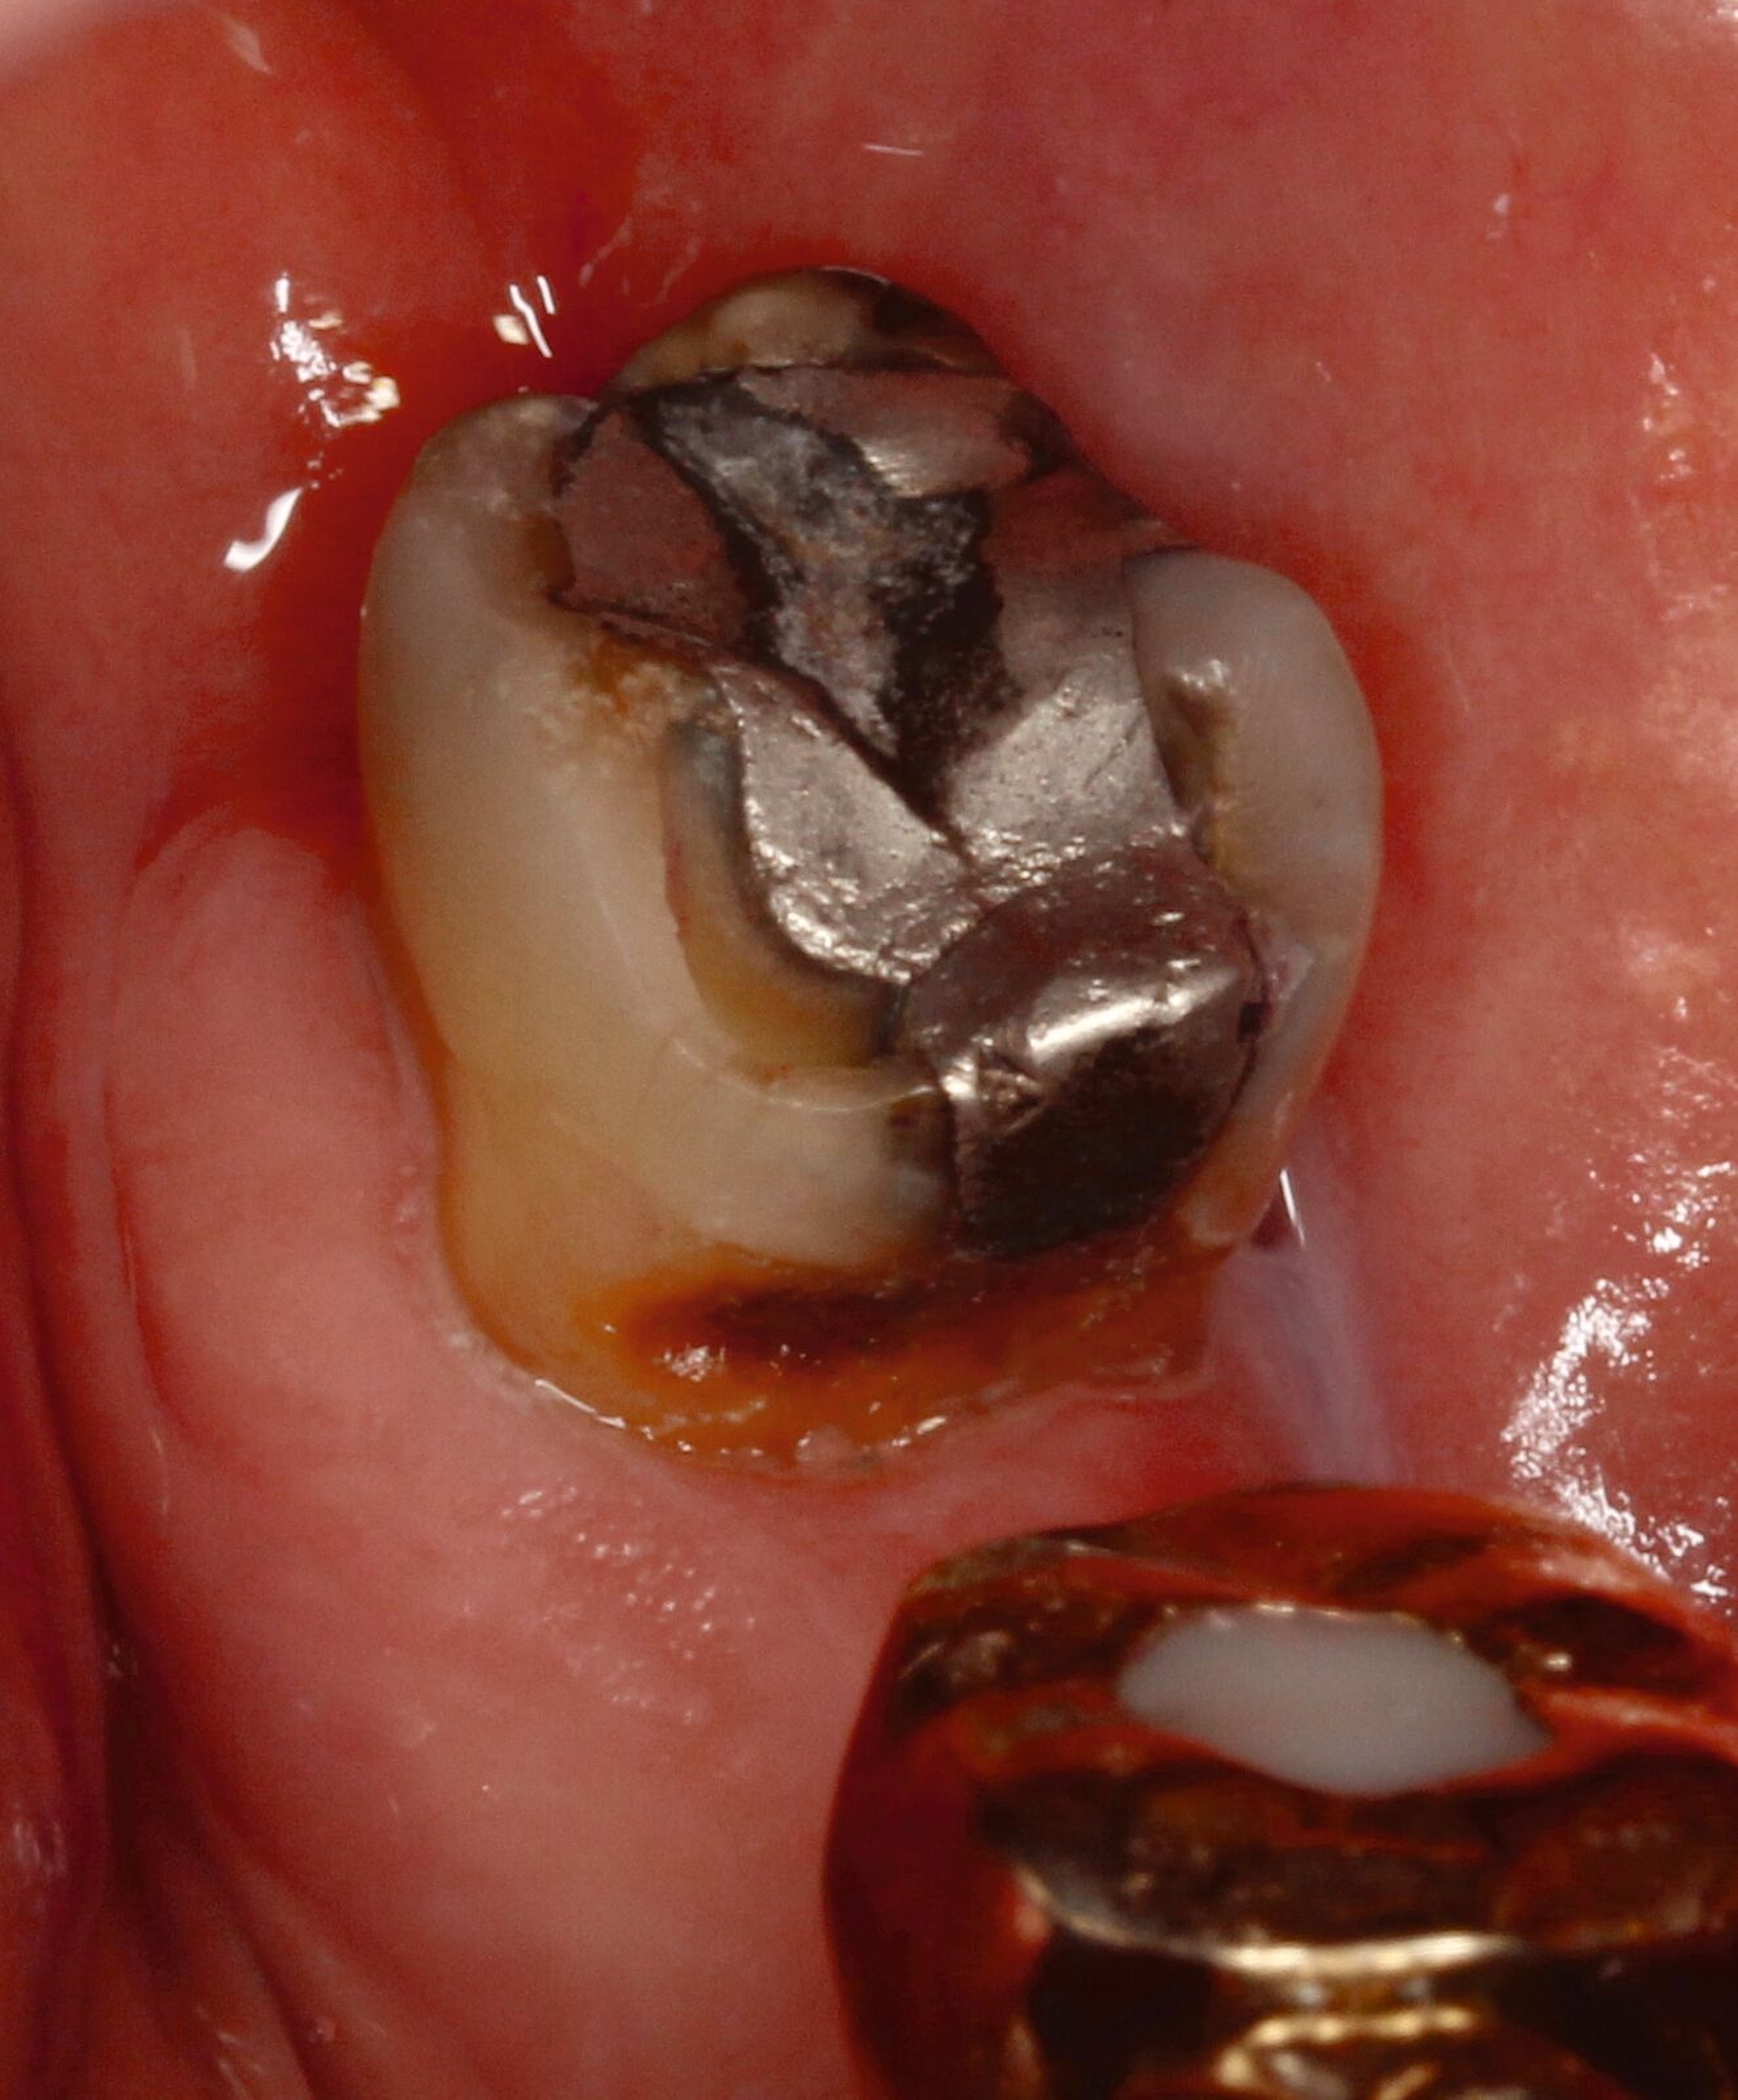

Eine bekannte Nebenwirkung bei Anwendung auf kariösen Läsionen ist die Schwarzfärbung des behandelten Bereichs (Abbildungen 3, 4). Verfärbungen können aber auch bei Applikation auf kariesfreien Wurzeloberflächen entstehen, diese sind jedoch mit einer professionellen Zahnreinigung gut zu entfernen (Abbildung 2).

Tatsächlich zeigt die klinische Erfahrung, dass es möglich ist, bei mehrmaliger Applikation innerhalb eines Vierteljahrs auch sehr aktive Läsionen mit taktil weicher Oberfläche trotz eingeschränkter Mundhygiene gut zu erhärten (Abbildung 4). Für die koronale Karies bei Kindern konnte die bessere Wirkung nach wiederholter Anwendung allerdings nicht bestätigt werden. [Smutkeeree et al., 2025].

Der Wirkungsmechanismus ist bislang nicht aufgeklärt. Die wesentlichen Verbindungen in SDF-behandelten Läsionen sind Silberphosphat, Silberoxid und Silbersulfid. Silberphosphat ist ein guter Photokatalysator [Yi et al., 2010], der spezifische chemische Reaktionen mit oder zwischen den verschiedenen beteiligten Verbindungen und Zahnstrukturen induzieren oder aber die auch ohne Licht eintretenden Reaktionen einfach beschleunigen könnte. Es wird vermutet, dass beispielsweise metallische Silbernanopartikel entstehen könnten [Li et al., 2019]. Abbildung 3 zeigt bräunliche Verfärbungen der Schleimhaut nach Lichteinwirkung.